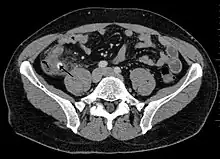

Computed tomography

Where it is readily available, computed tomography (CT) has become frequently used, especially in people whose diagnosis is not obvious on history and physical examination. Although some concerns about interpretation are identified, a 2019 Cochrane review found that the sensitivity and specificity of CT for the diagnosis of acute appendicitis in adults was high.[63] Concerns about radiation tend to limit use of CT in pregnant women and in children, especially with the increasingly widespread usage of MRI.[64][65]

The accurate diagnosis of appendicitis is multi-tiered, with the size of the appendix having the strongest positive predictive value, while indirect features can either increase or decrease sensitivity and specificity. A size of over 6 mm is both 95% sensitive and specific for appendicitis.[66]

However, because the appendix can be filled with fecal material, causing intraluminal distention, this criterion has shown limited utility in more recent meta-analyses.[67] This is as opposed to ultrasound, in which the wall of the appendix can be more easily distinguished from intraluminal feces. In such scenarios, ancillary features such as increased wall enhancement as compared to adjacent bowel and inflammation of the surrounding fat, or fat stranding, can be supportive of the diagnosis. However, their absence does not preclude it. In severe cases with perforation, an adjacent phlegmon or abscess can be seen. Dense fluid layering in the pelvis can also result, related to either pus or enteric spillage. When patients are thin or younger, the relative absence of fat can make the appendix and surrounding fat stranding difficult to see.[67]